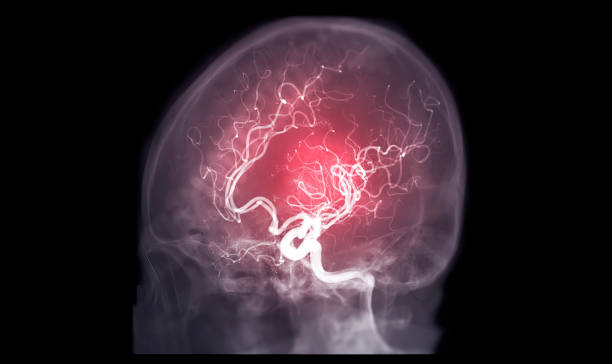

모야모야병 증상 제대로 알아보기

모야모야병은 중추신경계 질환 중 하나로, 이상한 소리와 자세, 신체적인 증상 등을 일으키는 질환입니다. 이 병은 실제로는 정신의학적인 질환으로 분류되며, 정확한 원인은 아직 알려지지 않았습니다. 하지만, 뇌의 신경전달물질인 도파민과 관련이 있을 수 있다는 가설이 제기되고 있습니다.

모야모야병의 특징은, 갑작스럽게 발생하는 이상한 소리와 자세, 그리고 다양한 신체적인 증상 등입니다. 환자는 자발적으로 특이한 소리나 움직임을 발생시키는 것이 아니라, 이것이 강제적으로 발생되기 때문에 어쩔 수 없이 소리를 내거나 움직임을 하게 됩니다. 이로 인해 일상생활에 큰 어려움을 겪을 수 있으며, 사회적인 이슈가 될 수도 있어 조기에 진단 후 치료를 받으셔야 합니다. 따라서 이번 시간에는 발생률이 높아지고 있는 모야모야병 증상에 대해 자세히 알아보겠습니다.